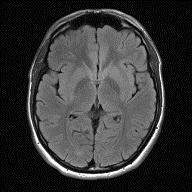

Anaberrantmassofcellsgrowingwithinoroutsideofyour brain is called a brain tumour. Brain tumours can be malignant, which is cancerous, or non-cancerous which is knownasbenign.

Fig.1. IllustrationsofCancerous&Non-CancerousCells (A) (B) (C)

(a)Normalimage.(b)Non-Cancerous(Benign).(c)Cancerous (Malignant).

Fig.2.IllustrationsofNormal,Benign,andMalignantimages.